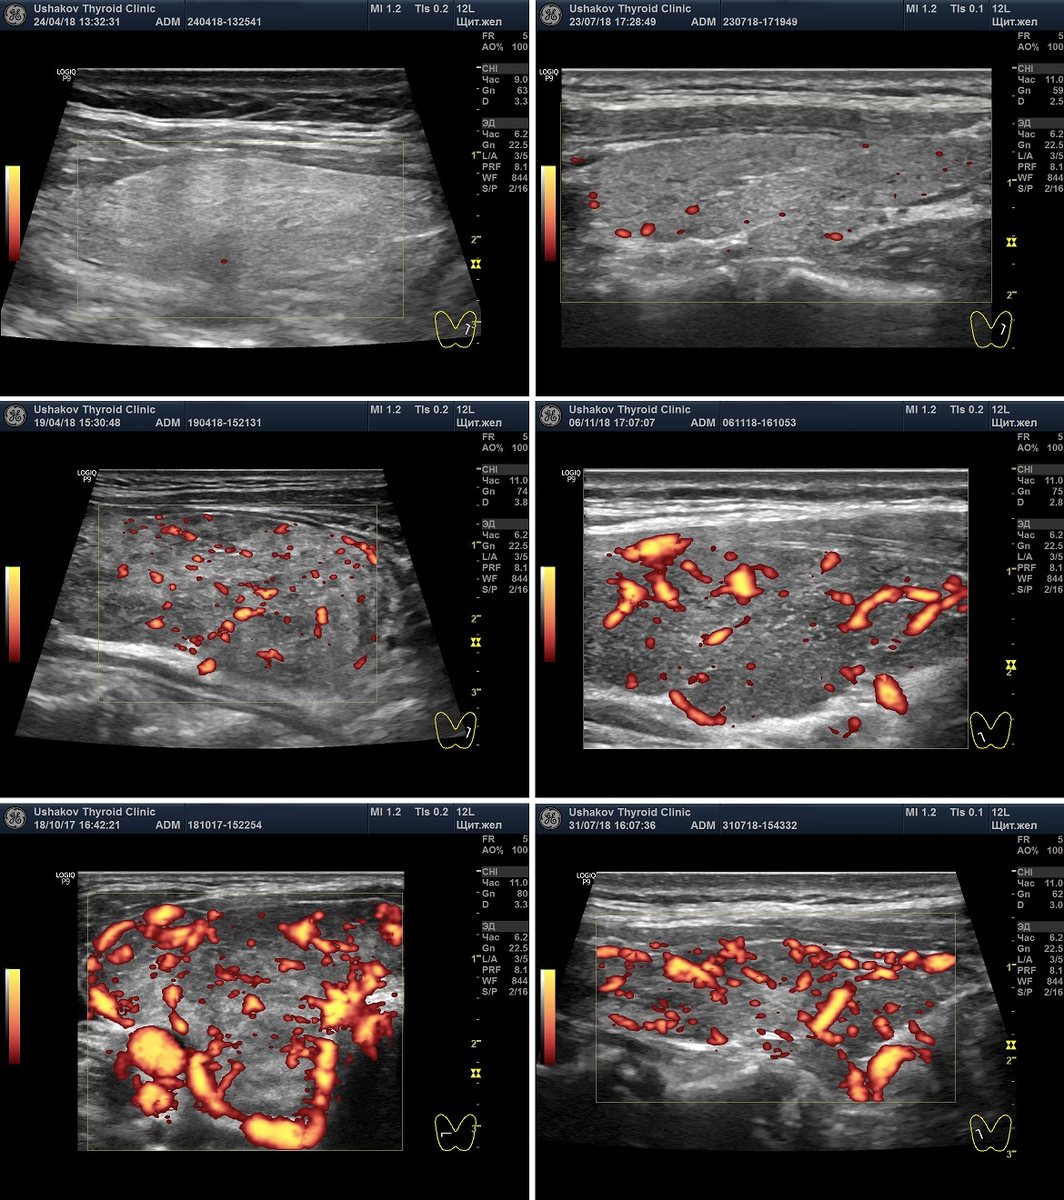

В режиме допплера (ЦДК или ЭДК) врач УЗД должен увидеть раскрашенные программой сосуды внутри щитовидной железы и по их количеству и расширению оценить как перенапрягается ( следовательно - истощается) ваша железа. Существует 6 вариантов состояния напряжения сосудистой сети в долях щитовидной железы.

Варианты кровотока в щитовидной железе при допплерографии в режиме ЭДК (энергетическое допплеровское картирование)